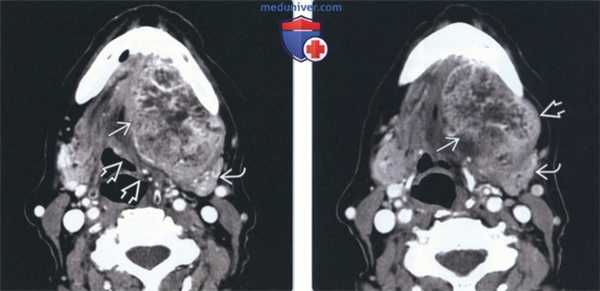

(Слева) На аксиальной КТ с КУ определяется очаговое гиподенсное образование. обусловливающее увеличение правой под нижнечелюстной железы (ПНЖ). Образование хорошо отграничено, что является признаком доброкачественности, но, тем не менее, требует патоморфологического подтверждения.

(Справа) На аксиальной КТ с КУ у другого пациента определяется неравномерное диффузное увеличение правой ПНЖ. Очаговое обызвествление с внутренней стороны позволяет заподозрить ДСО. Томография не позволяет различить злокачественную и доброкачественную опухоль за исключением случаев с явными признаками инвазии или лимфаденопатии. (Слева) На аксиальной МРТ (Т2 ВИ) у молодой женщины с пальпируемым образованием в поднижнечелюстной области в левой ПНЖ визуализируется хорошо отграниченная опухоль овальной формы с гиперинтенсивным сигналом. Признаки распространения опухоли за пределы ПНЖ отсутствуют.